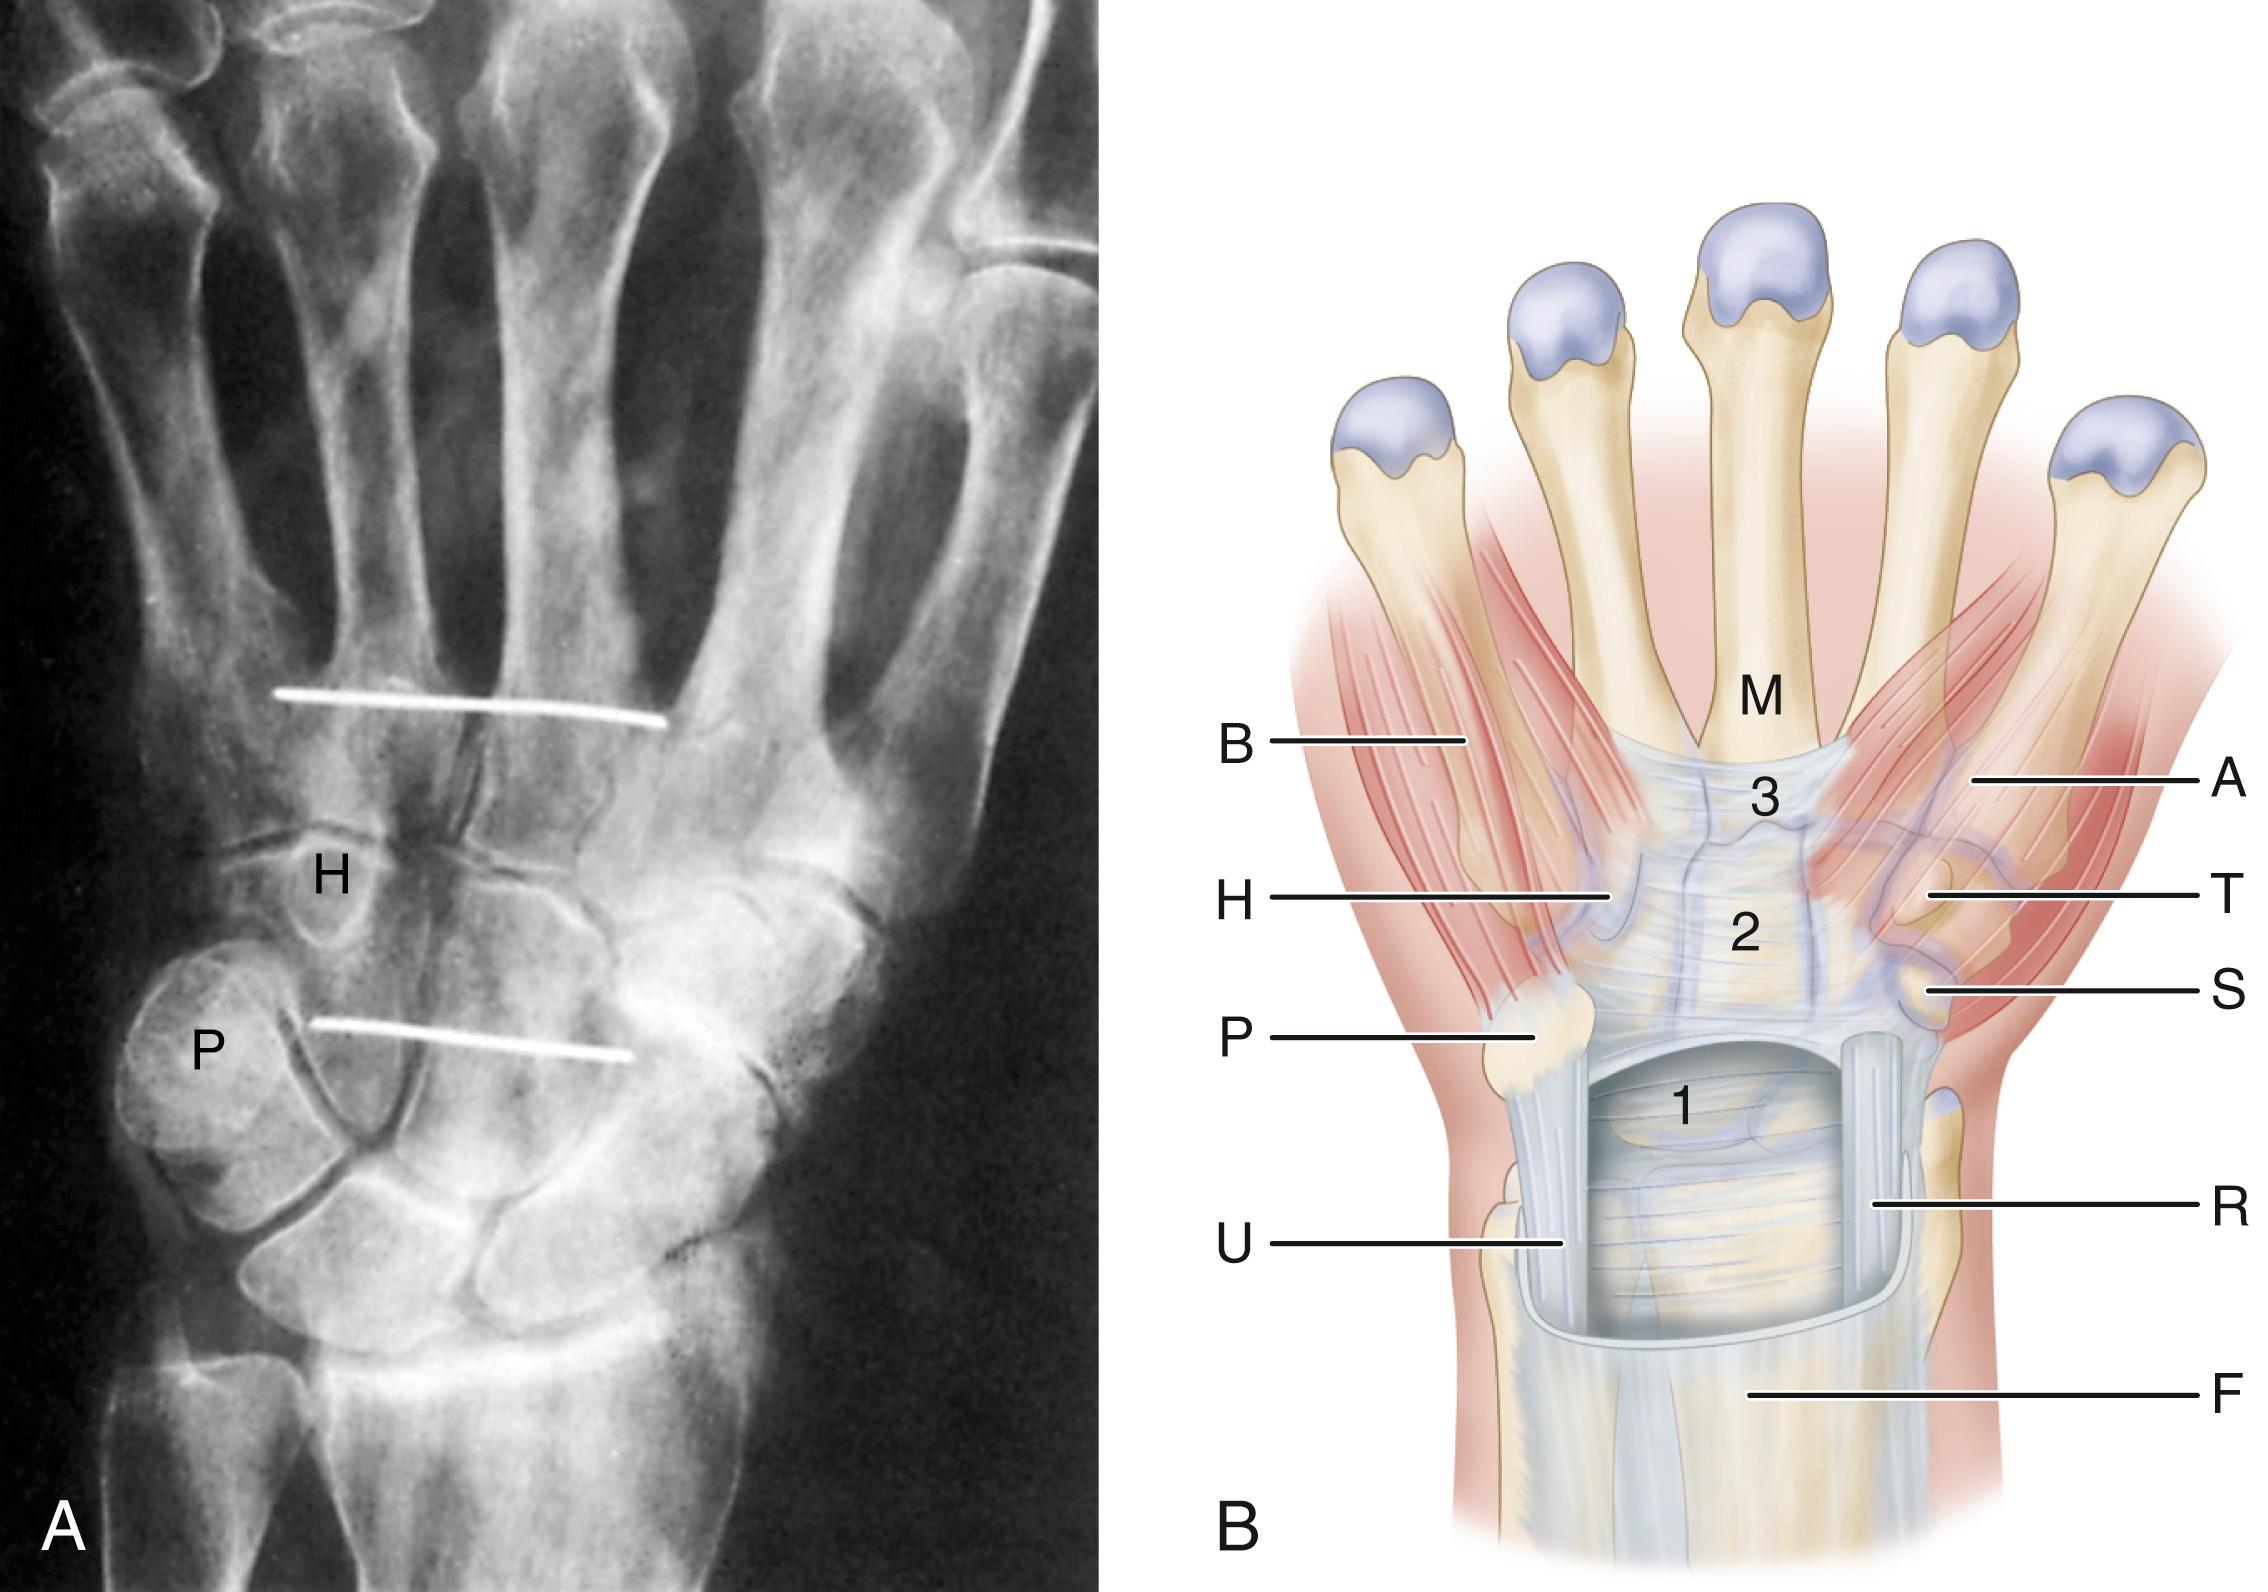

FIGURE 77.2, A, Anteroposterior radiograph of dissected right hand. Wires mark proximal and distal extents of classic flexor retinaculum, which includes middle portion of flexor retinaculum (transverse carpal ligament) and distal portion of flexor retinaculum. Note proximal limit is at distal aspect of pisiform (P) and distal limit is distal to hook of hamate (H) . B, Three portions of flexor retinaculum (1 to 3) consist of thick aponeurosis between thenar (A) and hypothenar (B) muscles. Thenar muscles attach to radial half of classic flexor retinaculum, composed of distal portion of flexor retinaculum (3) ; trapezial ridge (T) and scaphoid tubercle (S) also are shown. Proximal portion of flexor retinaculum (1) courses deep to flexor carpi ulnaris (U) and flexor carpi radialis (R) . Flexor carpi radialis tendon is shown as it pierces flexor retinaculum at junction of proximal and middle portions to enter its fibroosseous canal. F , Antebrachial fascia; M , third metacarpal.